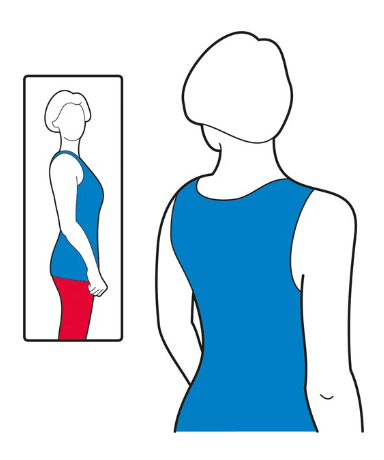

- بررسی وضعیت شانه:

قبل از شروع هر تمرین، وضعیت بدن خود را بررسی کنید. به پهلو بایستید، در آینه نگاه کنید و به آرامی شانه های خود را به سمت بالا و عقب حرکت دهید. سر و گردن باید آرام باشند و قفسه سینه باید کمی برجسته باشد، به طوری که انگار نفس عمیقی می کشید. به این حالت تنظیم کتف می گویند و نقطه شروع هر تمرین می باشد.